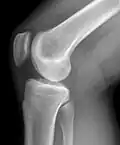

O joelho é uma articulação do corpo humano e de outros mamíferos. Formada pela extremidade distal do fêmur, pela extremidade proximal da tíbia (e pela patela (rótula).

O joelho ainda possui ligamentos que estabilizam a articulação, auxiliados pelos meniscos (interno ou medial e externo ou lateral), que estabilizam o joelho, e amortecem os impactos sobre as cartilagens.

A chave para uma articulação de joelho saudável é a estabilidade da articulação. A configuração óssea, os meniscos, os ligamentos, a cápsula e os músculos que cercam a articulação do joelho produzem a sua estabilidade.